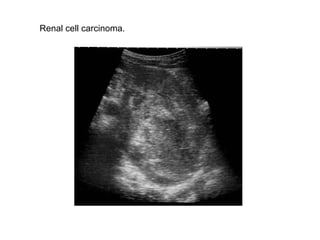

Renal cell carcinoma.